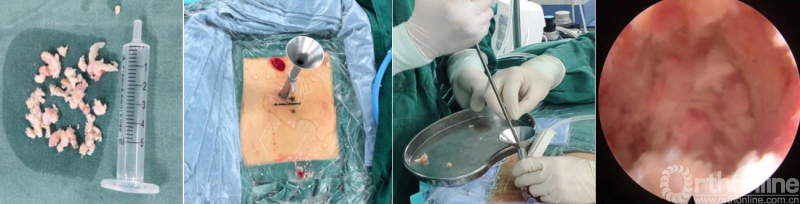

PE-PLIF技术十步法

详细步骤:一定、二辨、三凿、四分、五咬、六切、七旋、八铰、九填、十置

第一步“定”:X线定位在上位椎体下关节突下三分之一部;

第二步“辨”:镜下辨别下关节突关节囊;

第三步“凿”:凿除部分下关节突,显露上关节突及黄韧带;

第四步“分”:分离上关节突及黄韧带;

第五步“咬”:咬除部分上关节突,显露椎间盘及神经根;

第六步“切”:切除椎间盘;

第七步“旋”:旋转舌形套管保护神经根;

第八步“铰”:盲视下可撑开铰刀置入,撑开并处理上下终板;

第九步“填”;椎间隙填塞植骨;

第十步“置”:置入融合器、经皮钉。